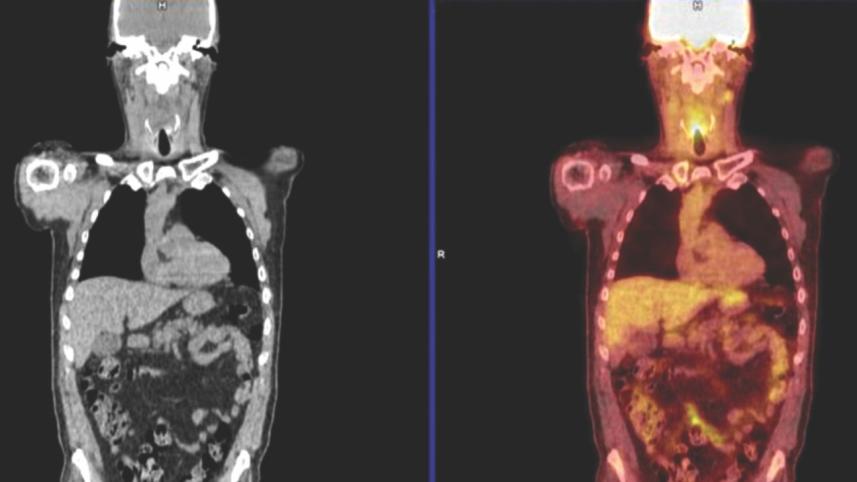

Positron emission tomography-computed tomography (PET-CT) uses a radioactive dye that is picked up by rapidly dividing cancer cells. This allows doctors to see if any of the head or neck cancer is still active.

Prof Hisham Mehanna, from the University of Birmingham, told the BBC, "Cancerous cells hide among the dead cells, with PET-CT you can call them out and find out whether they are alive or not. We can now use this new technology to save patients having a debilitating operation and identify those that need the operation rather than give it to everybody." Prof. Mehanna said scanning could help hundreds of thousands of people around the world each year.